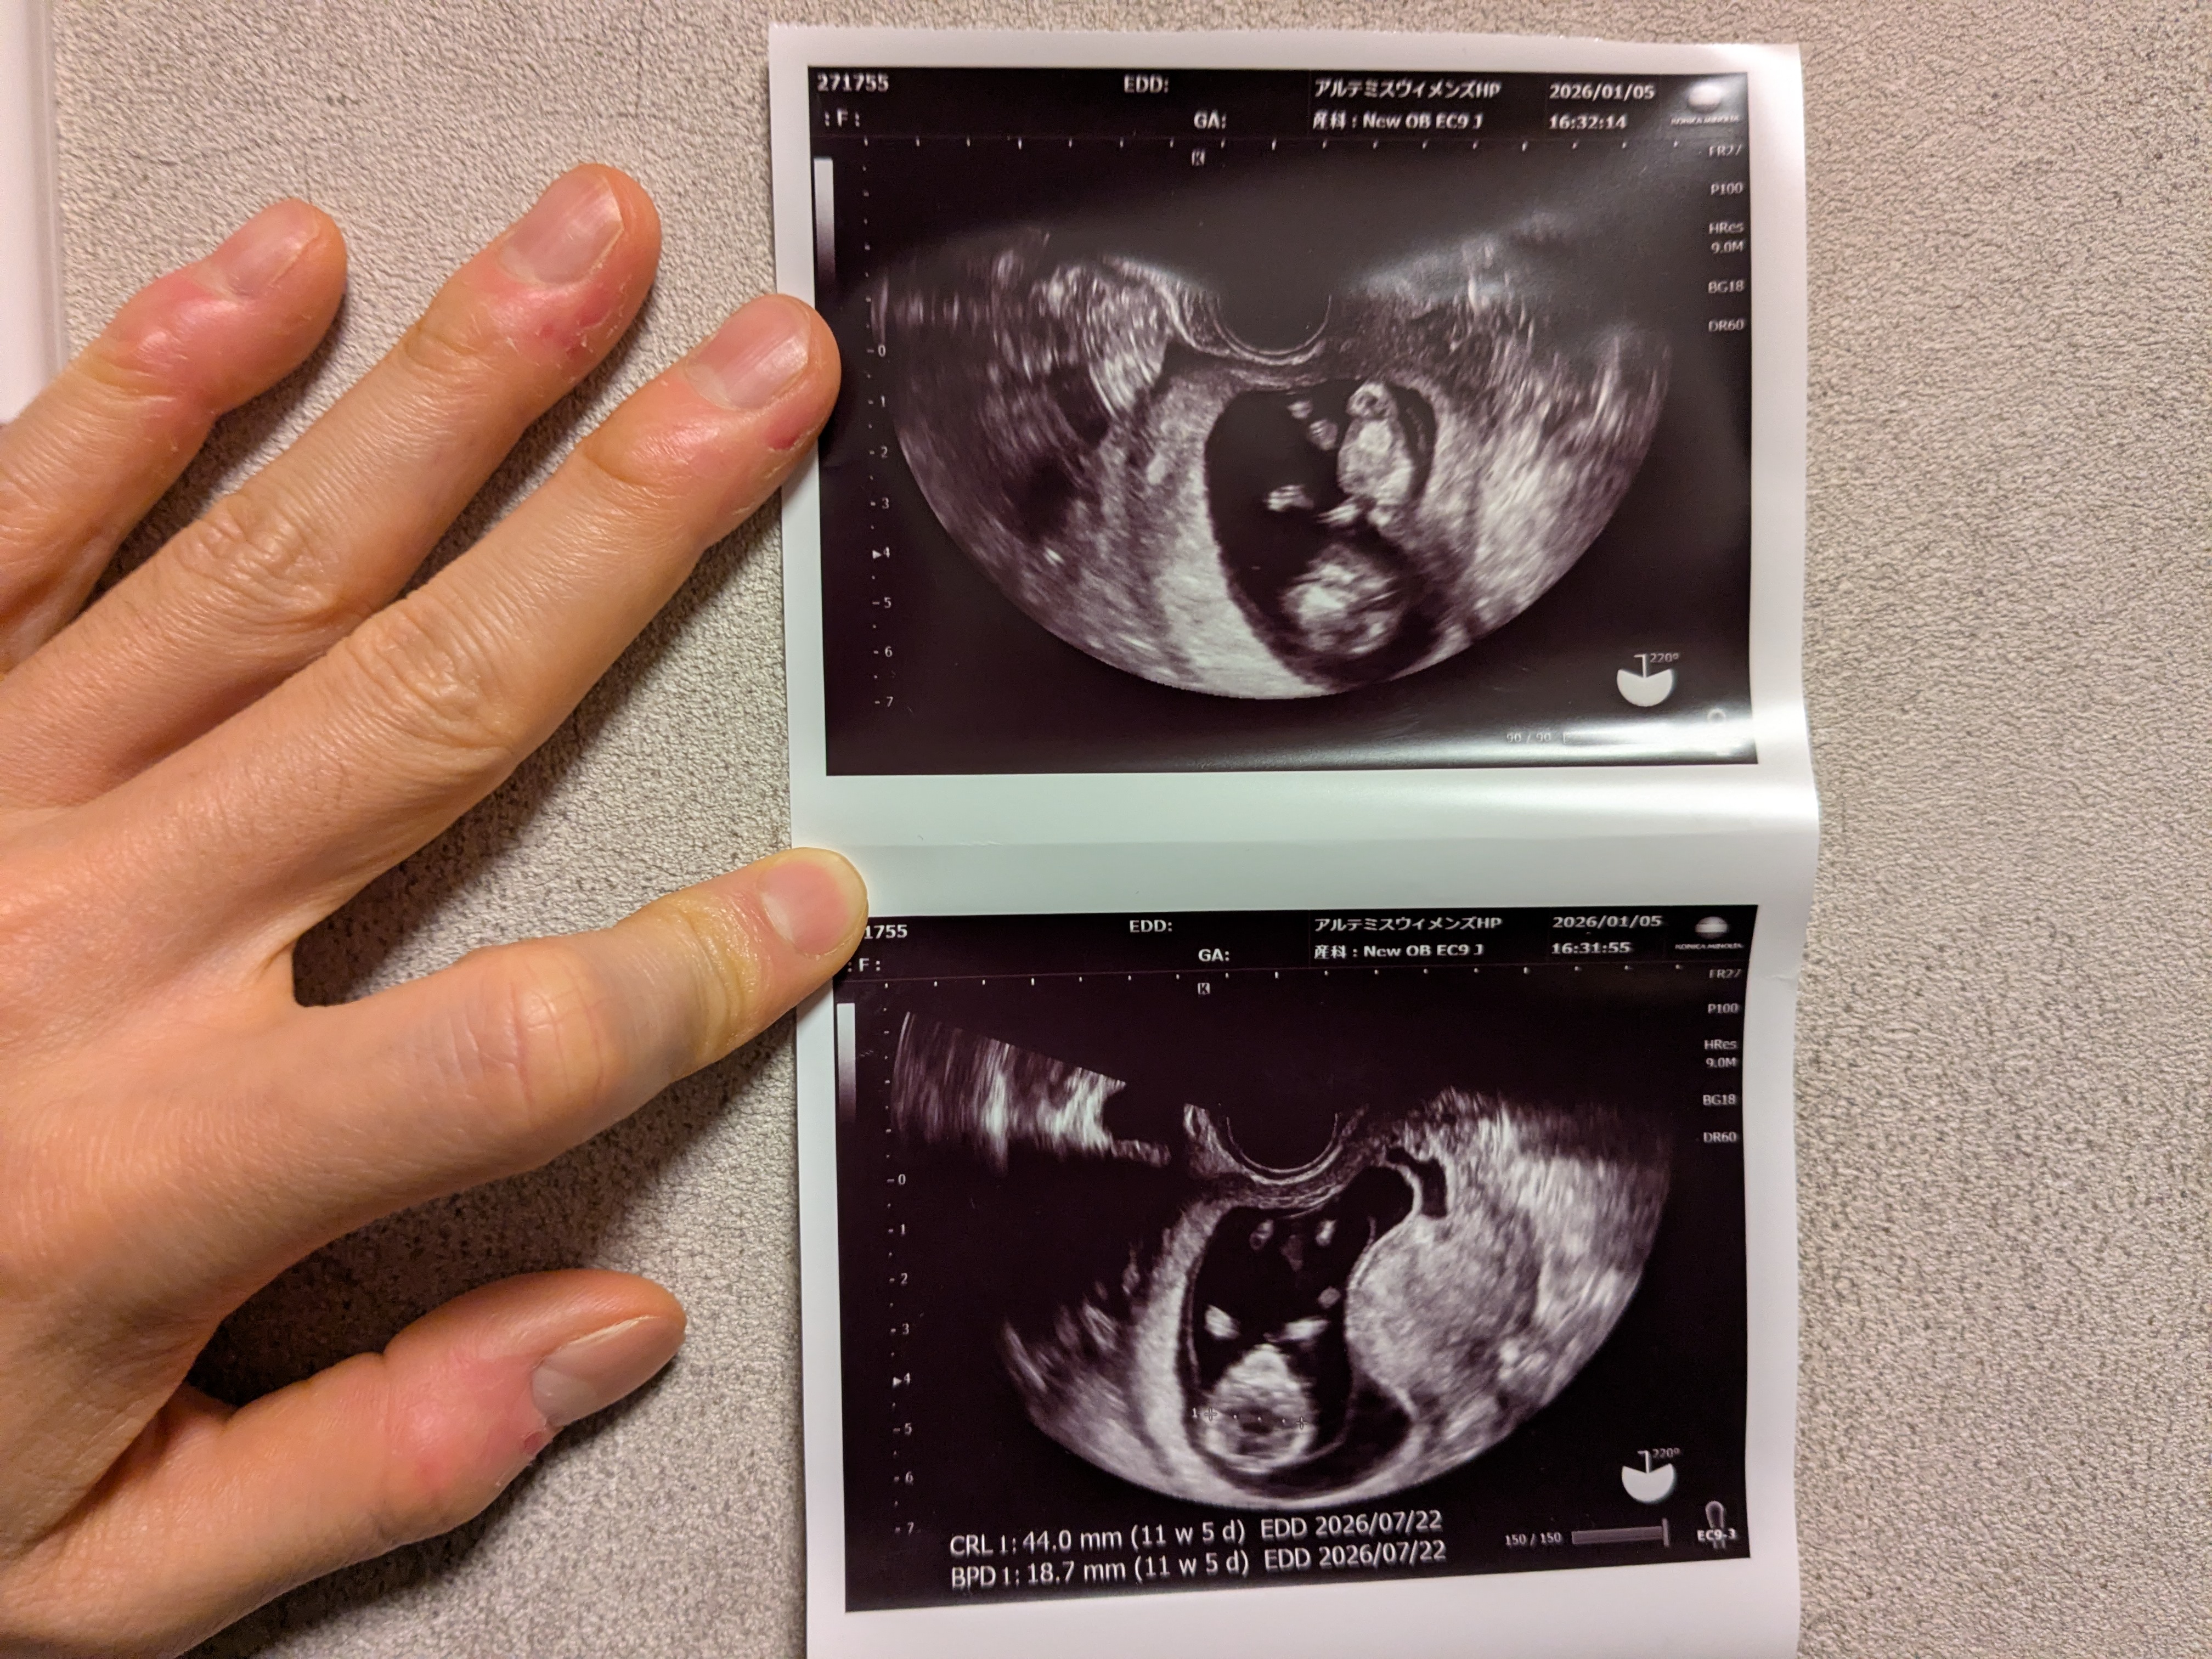

心拍が確認でき、CRL(全長)も44.0mmで平均並み!

また、BPD(頭の大きさ)も18.7mmで問題無し。

ちなみに頭が大きすぎるのはダウン症の特徴らしい。